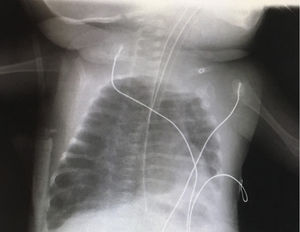

Paciente de 4 meses de edad, exprematuro de 24 semanas de gestación y con displasia broncopulmonar grave, conectado a ventilación mecánica (modalidad presión control con PIP 25cmH2O, PEEP 5,5cmH2O, FR 35rpm y FiO2 30%). El día que describimos, el paciente precisaba FiO2 de hasta el 50% y en la radiografía de tórax (fig. 1) mostraba hiperinsuflación intensa del hemitórax derecho y ausencia de deslizamiento pulmonar en la ecografía pulmonar (fig. 2). Dada la evolución de los pacientes con displasia broncopulmonar hacia la compresión dinámica de la vía aérea distal, se decidió incrementar progresivamente PEEP, sin mejoría ecográfica hasta llegar a una PEEP de 10cmH2O, donde se evidenció reaparición del deslizamiento pleural (fig. 3), y en la radiografía de tórax resolución parcial de la sobredistensión (fig. 4).